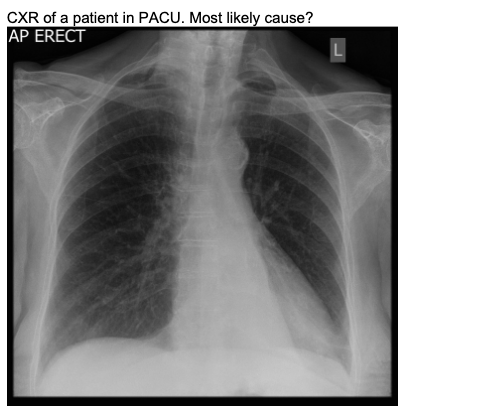

20.1 A 45-year-old man has poor oxygenation in the post anaesthesia care unit after a low anterior resection. His chest x-ray is below. The most likely diagnosis is

c